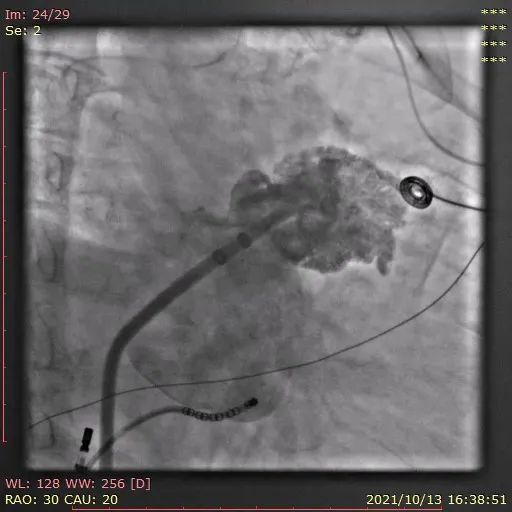

行左心耳头位和足位造影,造影显示左心耳为菜花型。锚定区约为20mm,开口区约为24mm,依据选型原则,拟选LAmbre™2228封堵器或2430封堵器。

图1:RAO30° CRA20° 头位造影

图2:RAO30° CAU20° 足位造影

图3:DSA测量图